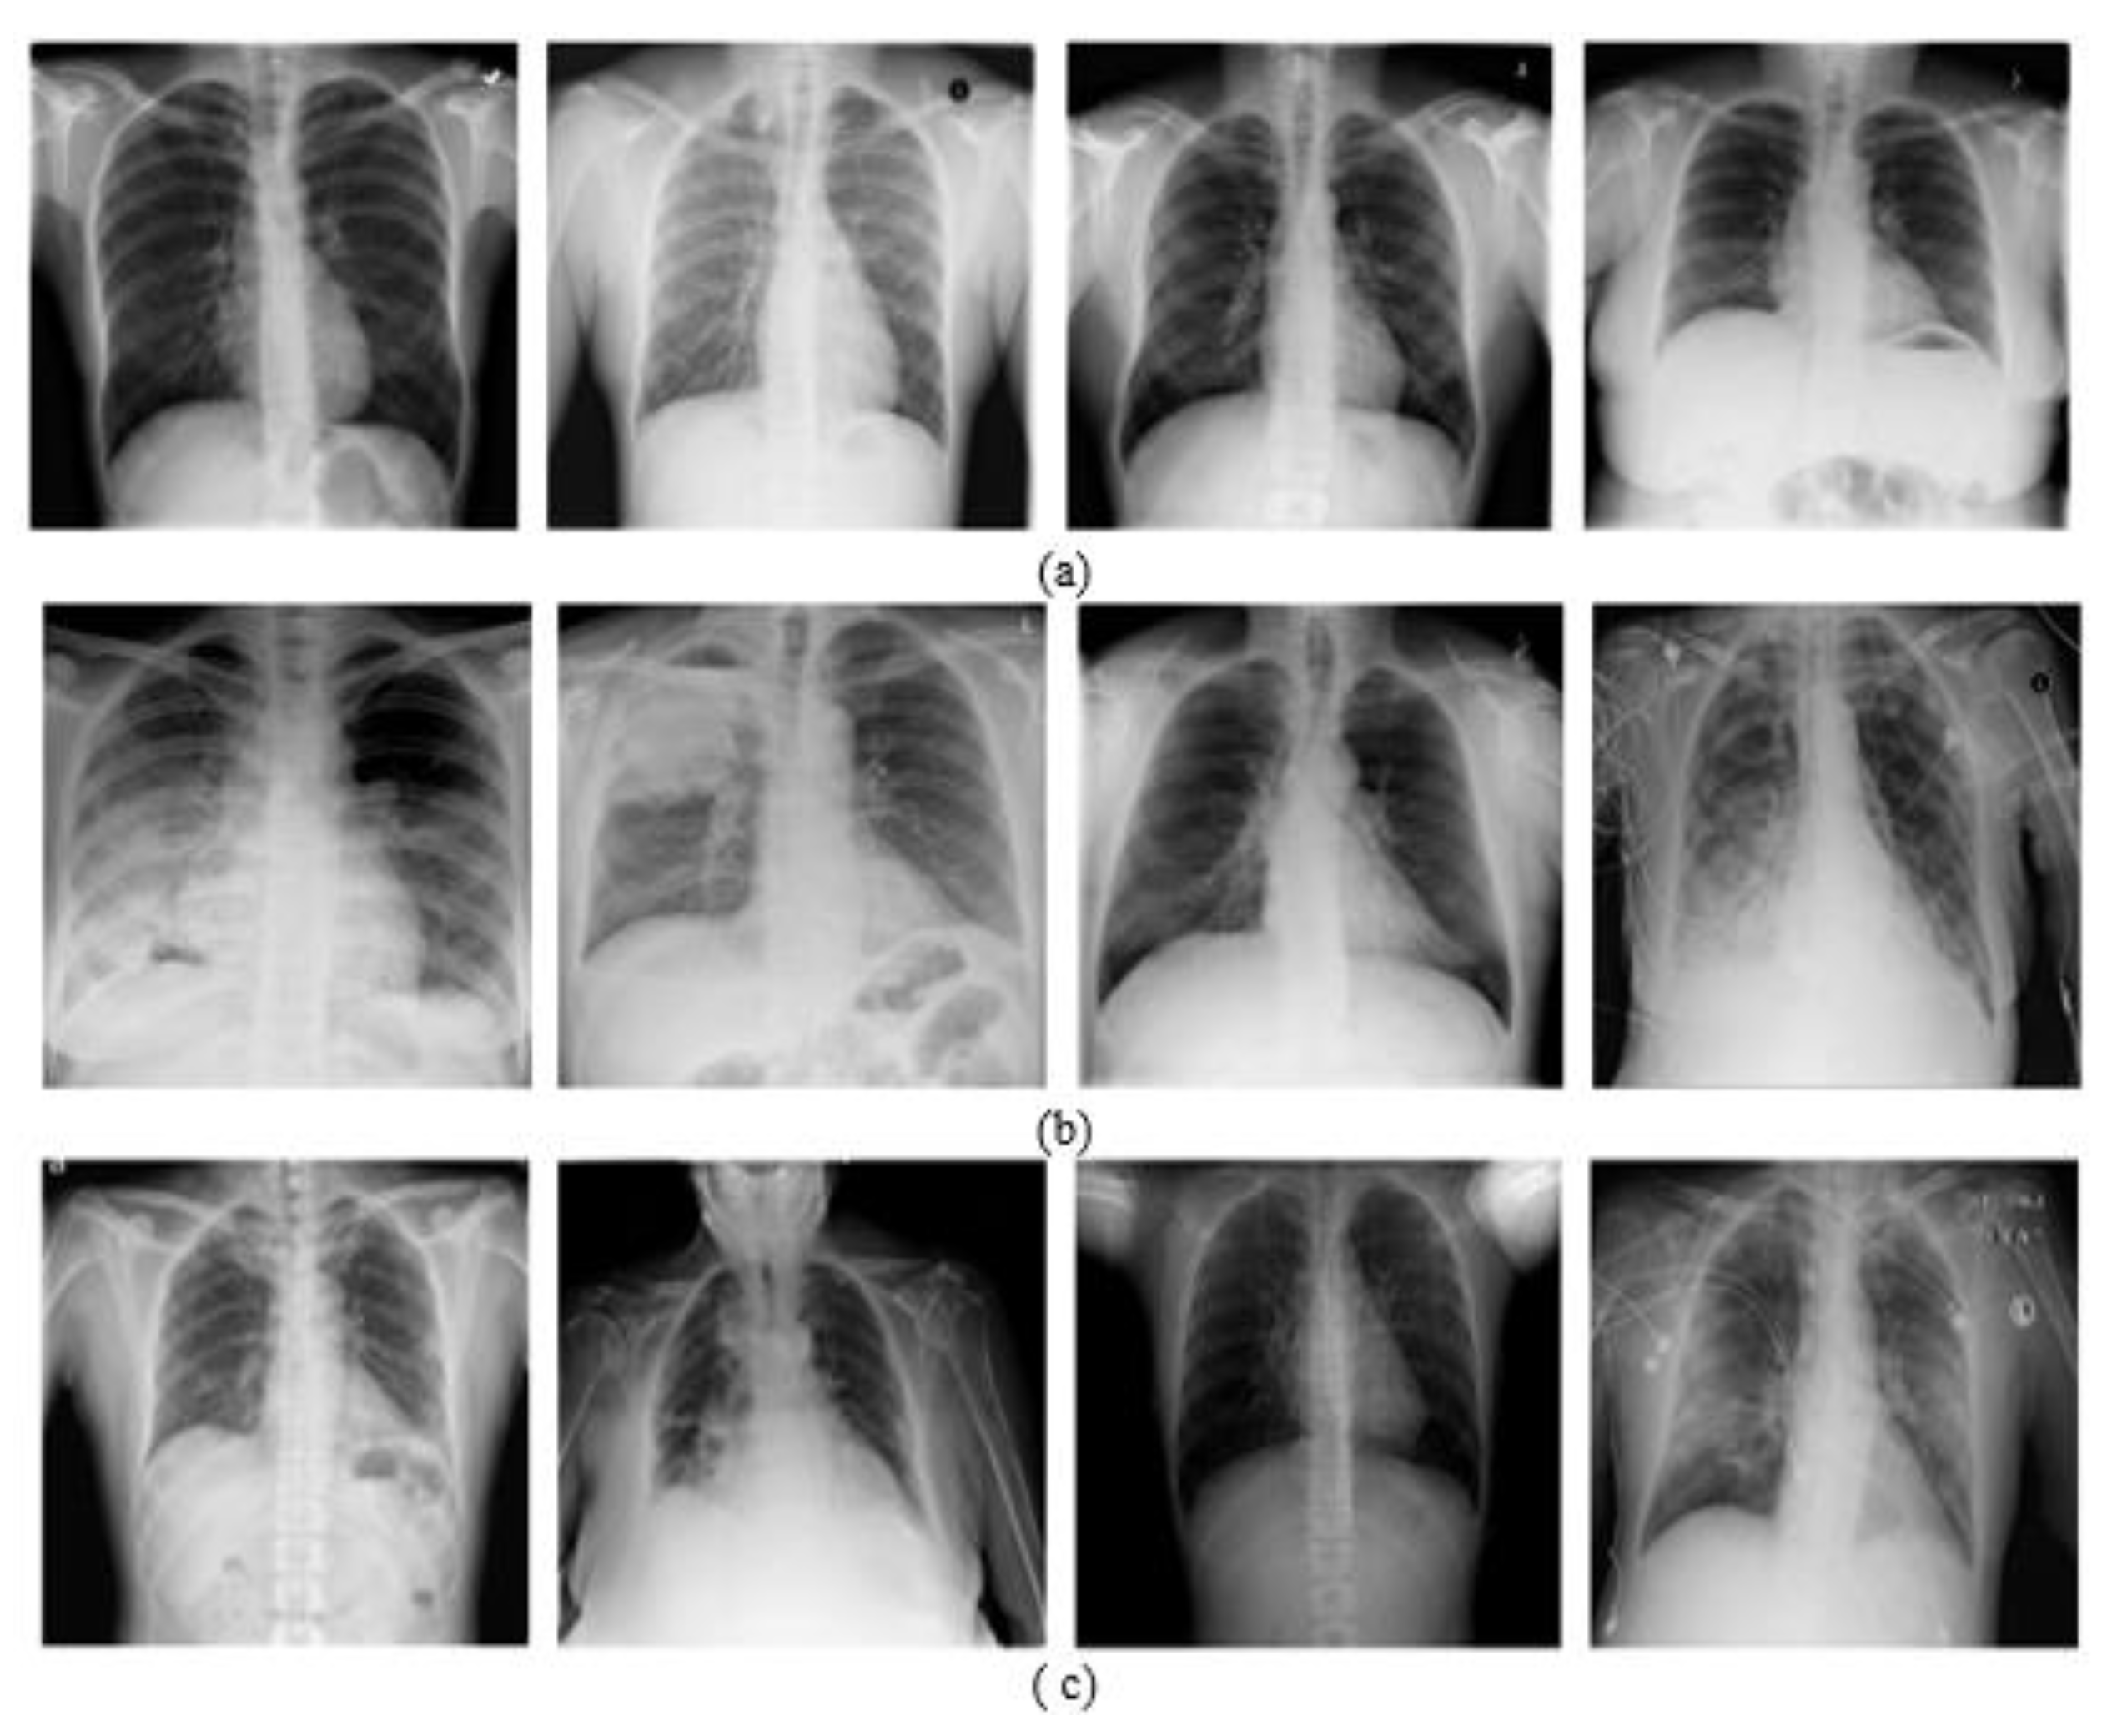

4.1.1. Chest X-ray Dataset

4.1.2. Chest X-ray Dataset